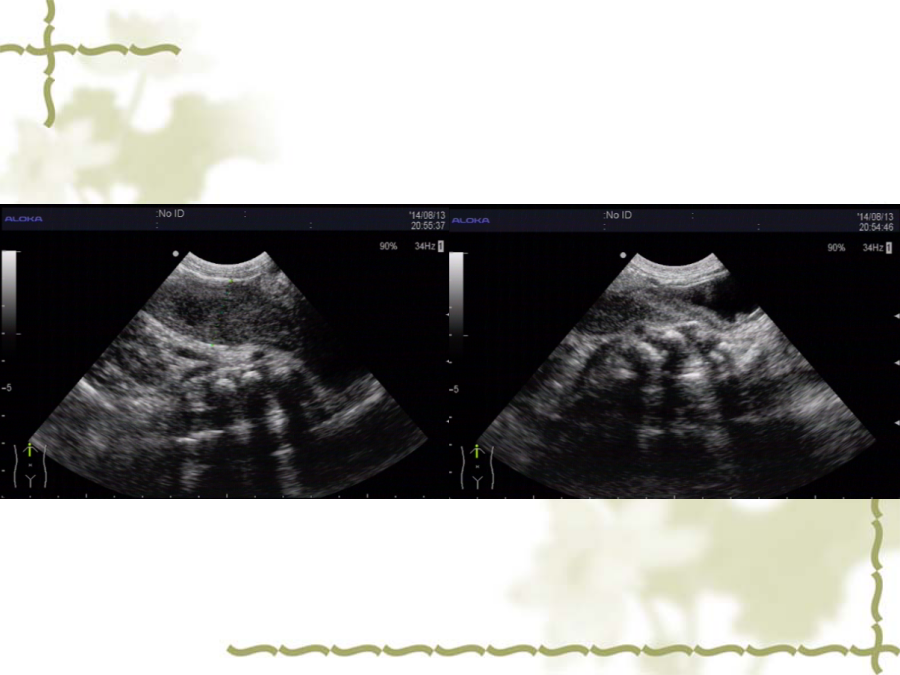

肛门闭锁的分类及超声表现患儿情况超声表现超声探查: 经肛穴处探查未探及明显肠管盲端, 经腹部探查于膀胱后方可见肠管盲端。 诊断: 肛门畸形(考虑:直肠高位闭锁) 腹部倒立位平片先天性直肠肛管畸形 最常见的消化道畸形 常伴发泌尿生殖系统及心脏神经性通畸形,约50%。 直肠肛管畸形分类(wingspread分类法1984)检查方法女性耻骨尾骨连线观察要点诊断标准(综合评价)谢谢感谢亲观看此幻灯片,此课件部分内容来源于网络, 如有侵权请及时联系我们删除,谢谢配合!